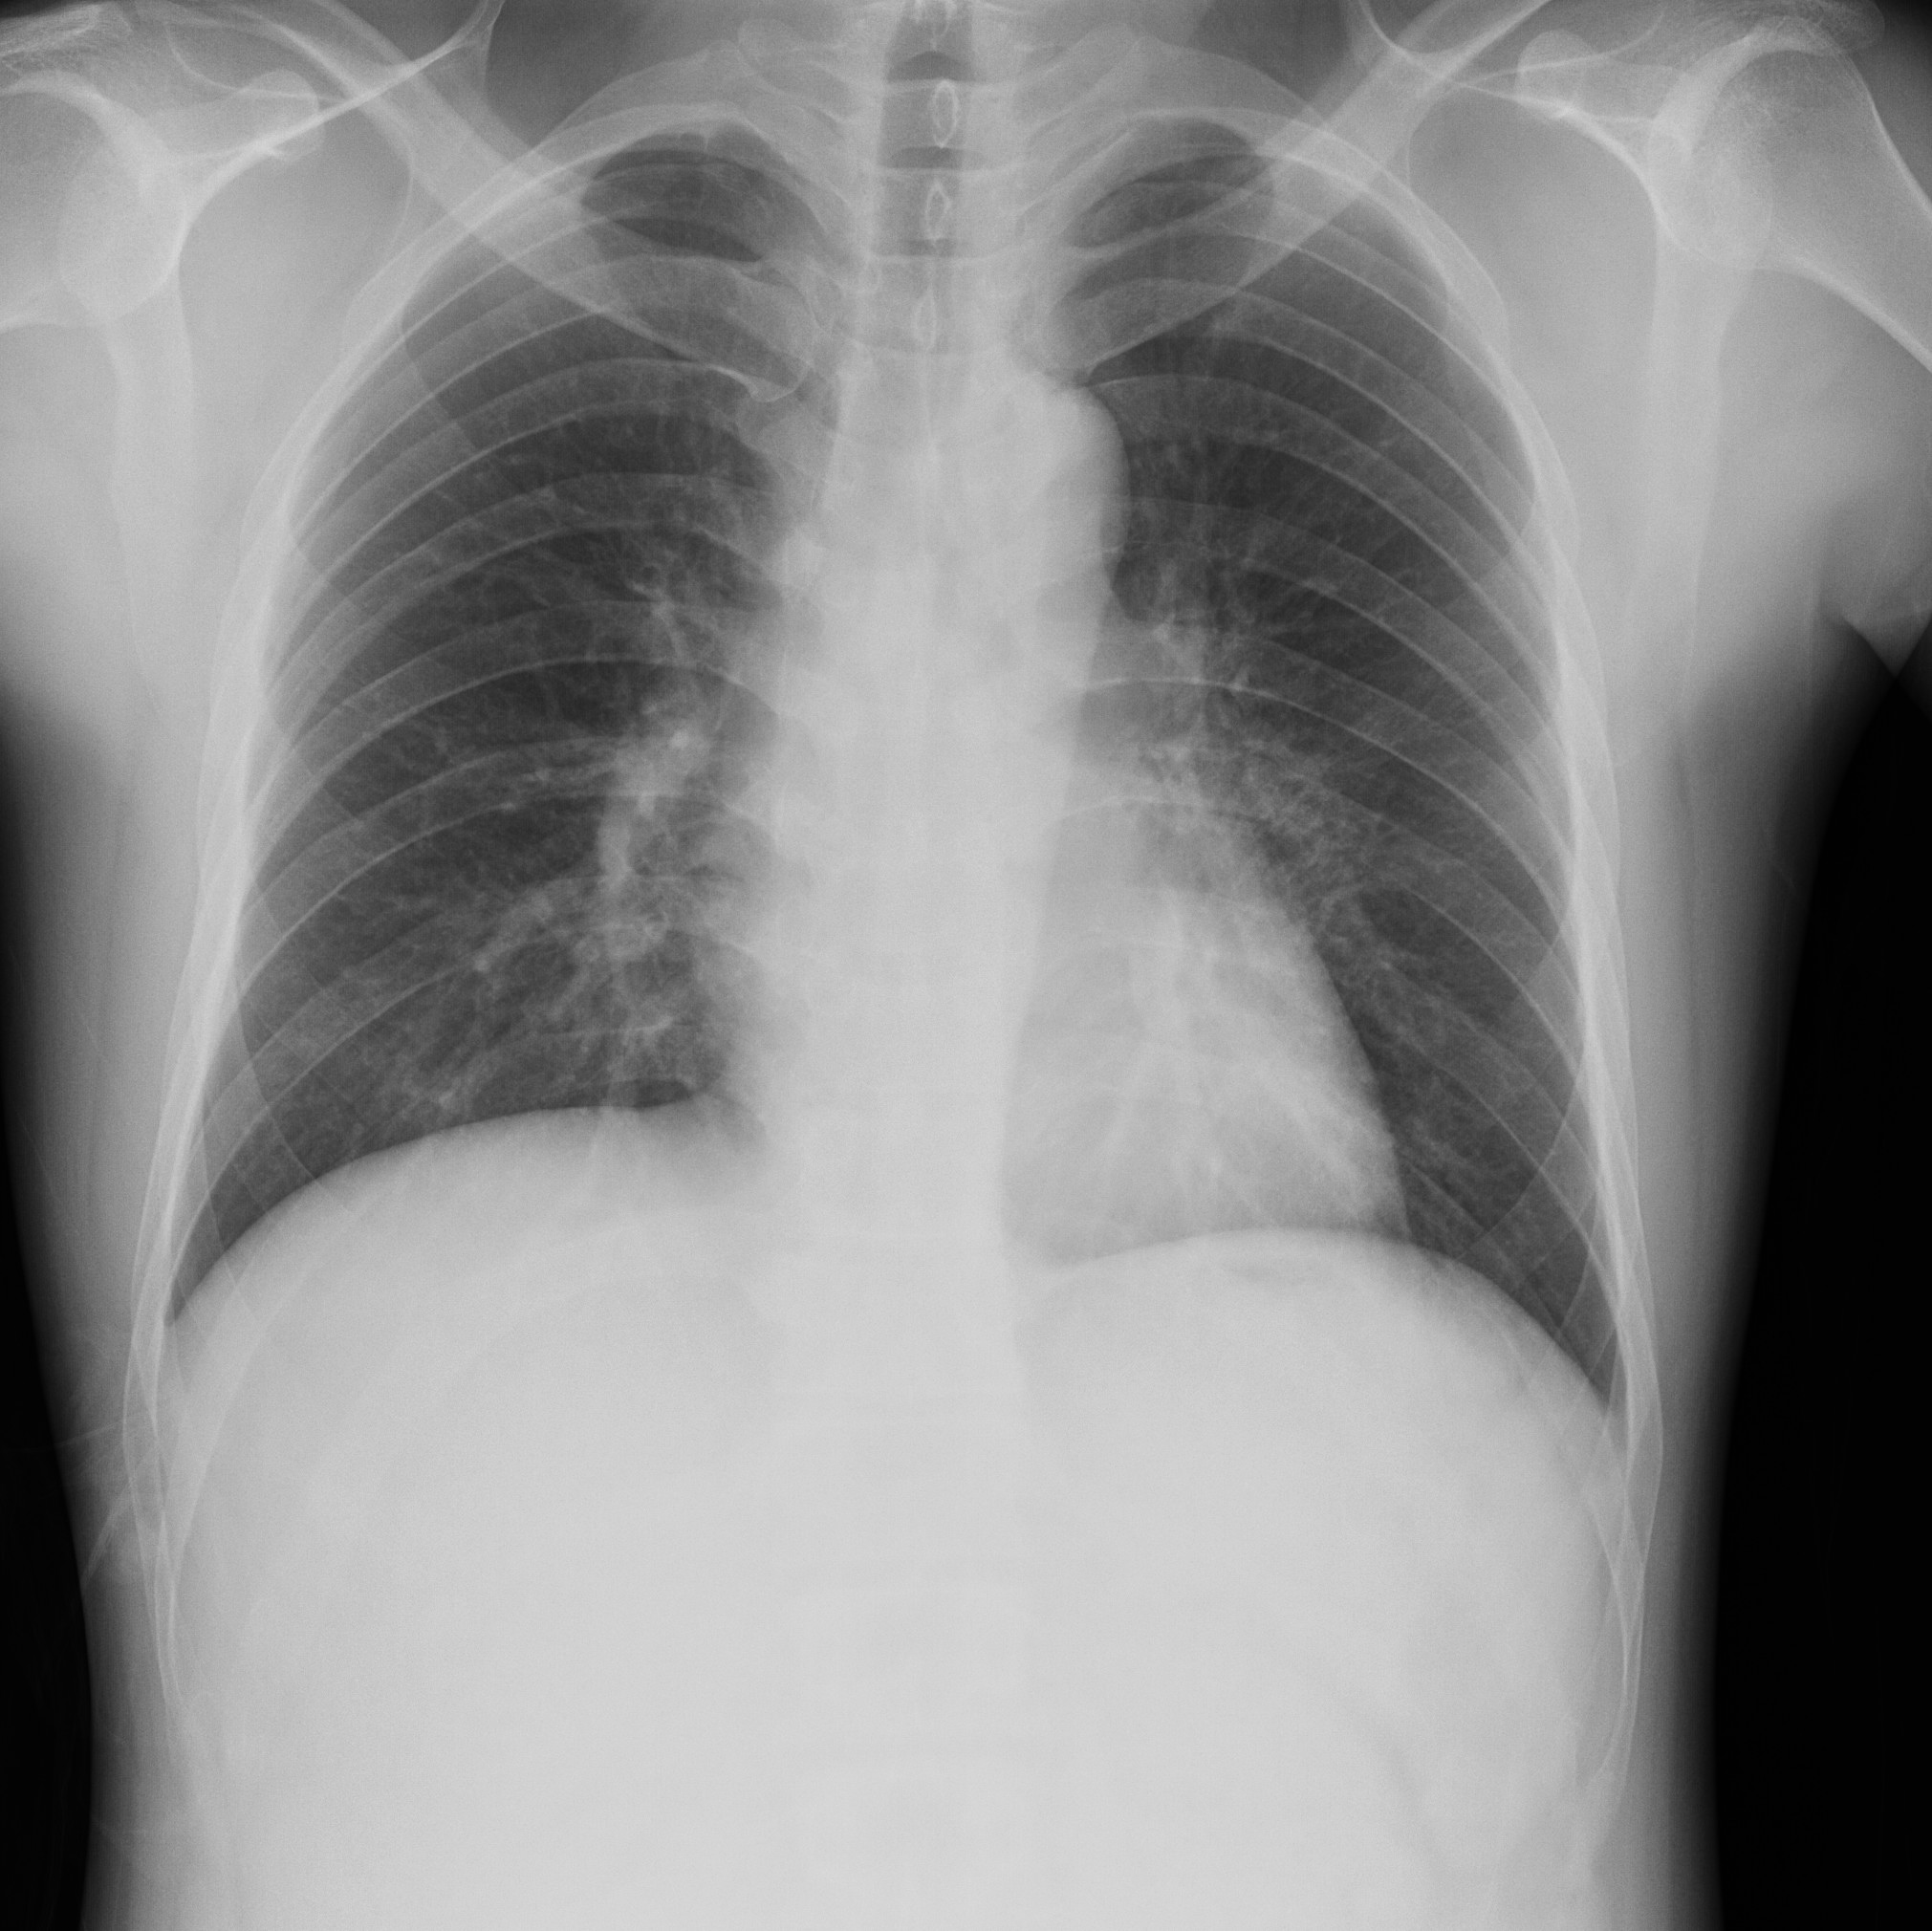

2012-04-13 chest PA